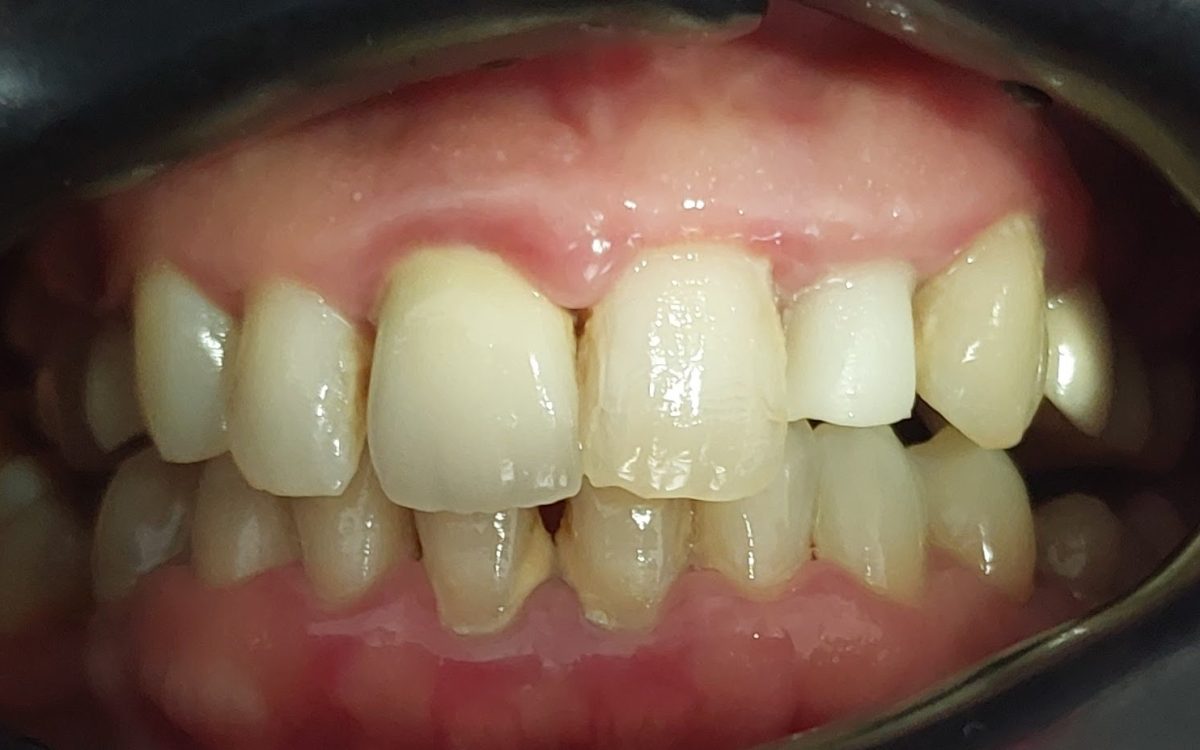

Gyökérkezelés

A gyökérkezelést a fogmegtartó, sőt, fogmegmentő kezelések közé soroljuk, hiszen a kezelés segítségével elkerülhető a fog eltávolítása.

Milyen tünetek esetén kerülhet szóba a gyökérkezelés?

- A fog érzékennyé válik: hidegre-melegre, rágás során, valamint egyéb külső ingerekre.

- Ráharapás során kifejezetten fájdalmat érzünk, ezért például kerüljük a rágást azon az oldalon

- Nem érzünk fájdalmat, de kontrollvizsgálatkor röntgenen a fog körül elváltozás látszik

- A fog nagyobb darabja letörik

- Feltűnő elszíneződés a fogon, mely a többi fogat nem érinti

- Kisugárzó akut fájdalom esetén amennyiben az fog eredetű

- Fogpótlások előkészítése során megnyíló fogbél esetén

Minden esetben több tényezőt vizsgálunk a javaslat megtétele előtt, amennyiben a kiváltó ok megszüntetésére és a fog megtartására is alkalmas a gyökérkezelés, elsőként választandó terápiának ezt javasoljuk.

Hogyan zajlik a gyökérkezelés?

- A fogorvos érzéstelenítés után megnyitja a fogat a rágófelszín felől. A gyökérkezelések gyakran abszolút izolálásban, kofferdam lepedő segítségével történnek.

- Eltávolítja a fogbélkamra tartalmát, felkeresi a gyökércsatornákat, ezeket tágítja, formázza, fertőtlenítő oldatokkal átmossa, majd kiszárítja.

- Első alkalommal gyakran ideiglenes, gyógyszeres töméssel látja el a fogat, mely a gyulladás csökkentésében és a fertőtlenítésben játszik fontos szerepet.Alkalmanként a gyógyszeres tömés cseréjére szükség lehet erősebb gyulladás, fennmaradó panaszok esetén.

- A gyökereket speciális gyökértömő anyaggal látjuk el.

- A fogorvos elkészíti a fog látható részének helyreállítását. Ez történhet töméssel, koronával, vagy betét készítésével.

Egy jól elvégzett gyökérkezelés az erősen fájó, gyulladt fogakat is képes hosszú évekre megtartani, és tünetmentessé tenni.